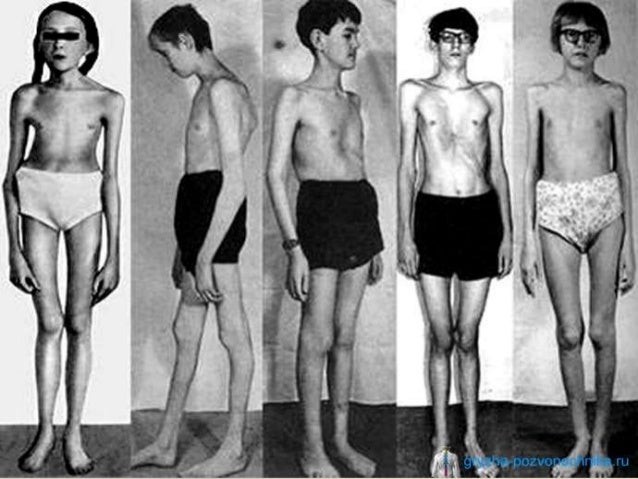

Neonatalnaya forma sindroma marfana klinicheskoe opisanie i kompleksnyj podhod k diagnostike i lecheniyu tema nauchnoj stati po klinicheskoj medicine chitajte besplatno tekst nauchno issledovatelskoj raboty v elektronnoj biblioteke kiberleninka (Тип файлу jpg)

Neonatalnaya Forma Sindroma Marfana Klinicheskoe Opisanie I Kompleksnyj Podhod K Diagnostike I Lecheniyu Tema Nauchnoj Stati Po Klinicheskoj Medicine Chitajte Besplatno Tekst Nauchno Issledovatelskoj Raboty V Elektronnoj Biblioteke Kiberleninka

Neonatalnaya forma sindroma marfana klinicheskoe opisanie i kompleksnyj podhod k diagnostike i lecheniyu tema nauchnoj stati po klinicheskoj medicine chitajte besplatno tekst nauchno issledovatelskoj raboty v elektronnoj biblioteke kiberleninka (Тип файлу jpg)

Neonatalnaya Forma Sindroma Marfana Klinicheskoe Opisanie I Kompleksnyj Podhod K Diagnostike I Lecheniyu Tema Nauchnoj Stati Po Klinicheskoj Medicine Chitajte Besplatno Tekst Nauchno Issledovatelskoj Raboty V Elektronnoj Biblioteke Kiberleninka